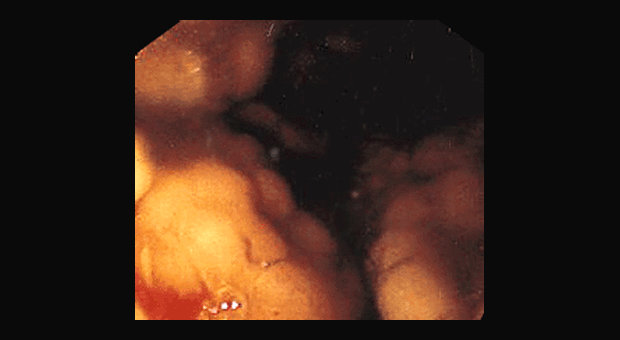

Иллюстрация №2: Лимфома желудка

Несмотря на достаточно редкую встречаемость лимфомы желудка эндоскопическая диагностика данного состояния весьма не легка. Пациентам с лимфомами желудка при эндоскопическом исследовании достаточно часто выставляются диагнозы иных (доброкачественных) заболеваний. Диагностировать же эту патологию на ранней стадии, до перехода ее из низко в высоко злокачественную форму крайне важно для дальнейшего прогноза.

Лимфома с поражением желудка встречается в 1-5% среди всех желудочных болезней. Однако в последние годы наблюдается значительная тенденция роста этого показателя, включая заболевание у молодых людей. Большая часть этих опухолей происходит из лимфоидной ткани, ассоциированной со слизистой оболочкой, На сегодняшний день главная роль в начале её развития отводится НР инфекциям, на фоне которых происходит появление лимфоидных фолликулов в слизистой оболочке желудочной стенки. Прогноз выживаемости при этом заболевании разнится в зависимости от возраста больного, времени диагностирования и эффективности терапии. По разным источникам, пятилетняя выживаемость составляет 50%.